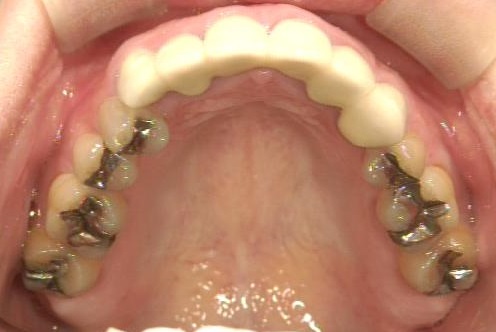

治療前

治療後

- 治療内容

- 臼歯部インレー 6本

- 費用

- 390,000円(税別)〜

- 治療期間

- 約一か月

- リスク・副作用

- 30代女性。金属を白くやり替えたいと受診。食いしばりがあるためe.maxを選択。「金属の味がしなくなりました」と満足していただけました。

セット後、破折のリスクがあるためナイトガードの使用を勧めました。